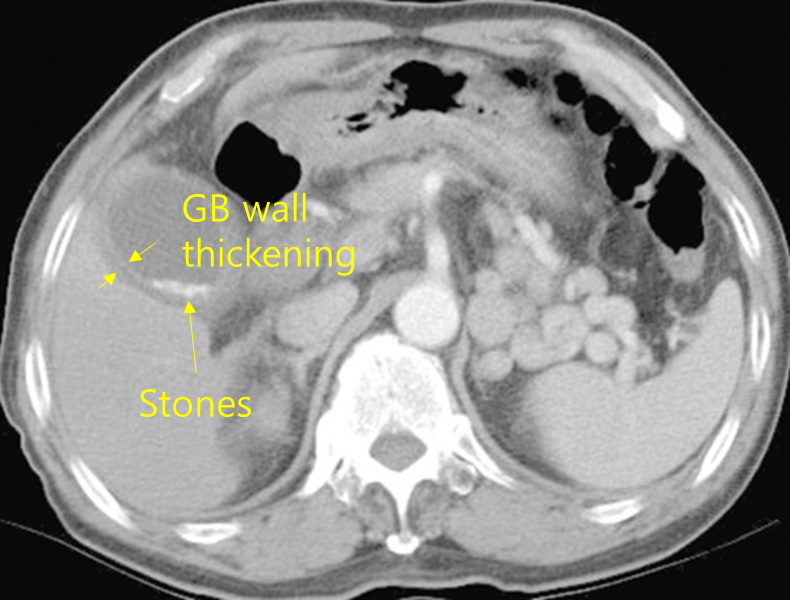

78세 남자가 3일 전부터 오른쪽 윗배가 아프다고 병원에 왔다. 심한 만성폐쇄폐질환으로 3년 전부터 산소요법을 받고 있다고 한다. 혈압 80/50 mmHg, 맥박 110회/분, 호흡 22회/분, 체온 38.9℃이다. 의식은 졸리는 상태이고 오른쪽 윗배에 압통이 있으나 반동압통은 없다. 혈액검사 결과는 다음과 같다. 복부 컴퓨터단층촬영 사진이다. 적합한 치료를 고르시오 (한 가지).

Img | CT: GB stones |

우상복부 통증을 호소하는 환자로, 발열과 leukocytosis가 있으며, CT 상에서 담낭 내에 담석이 관찰되므로 급성 담낭염을 의심할 수 있다. 급성 담낭염의 치료는 (단순)쓸개절제술이지만, 증례의 환자는 고령이고, 산소 요법을 필요로 할 정도의 심한 COPD가 있으며, V/S instability가 동반되어 있어 당장 수술은 어려운 상태다. 따라서 피부간경유쓸개배액술(PTGBD)을 시행하여 우선 담낭 내의 담즙을 배액해 주어야 한다.

진단 | • US(1st line), CT: GB stone, GB wall thickening, pericholecystic fluid |